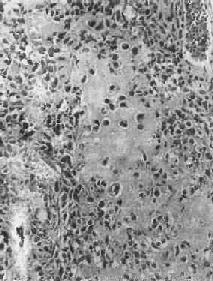

镜下,肿主要由单核基质细胞及多核巨细胞等两种细胞组成(图17-6),间质血管丰富。基质细胞为梭形、卵圆形或圆形,细胞境界不清楚,常见胞浆突起。细胞核较大,染色质量中等,可具有一个核仁。多核巨细胞常较均匀地散布在基质细胞之间,是为本的特点。多核巨细胞的直径常为30~60μm,核数一般为15~20个,最多可达100个以上,常聚集在细胞的中央。核的形态与单核基质细胞相似。细胞边界不规则,但分界较清楚,胞浆丰富,略呈嗜碱性,有时还可见含大量脂类的泡沫细胞。本间质血管丰富,有多少不等的胶原纤维。肿本身无成骨现象,但有时见有类骨组织及新生骨小梁,常见于纤维组织的周围,可能是一种反应性新骨形成或病理性骨折后形成的骨痂。

图17-6 骨巨细胞(Ⅰ级)

由大量基质细胞和多核巨细胞两种细胞组成